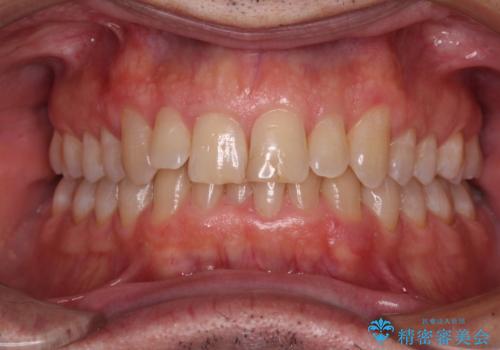

【モニター】前歯のデコボコを治したい インビザライン矯正治療

- 前歯のデコボコを気にして来院された患者様です。

インビザラインでもワイヤー装置でも対応可能でしたが、仕事の都合で来院回数を減らしたいとのことでインビザラインによる矯正治療を選択されました。

著しく咬合力が強いため、奥歯がしっかりと噛めずに治療が長引くことが懸念されました。

1セット目のインビザラインを使用した際には左右ともに大臼歯が咬み合っていなかったのですが、2セット目できっちりと仕上げることができました。